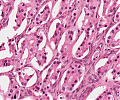

A92 Follikuläres Adenom der Schilddrüse

Randlicher Anteil mit mikrfollikulärem Aufbau (hohe Vergrößerung)

A92 Follikuläres Adenom der Schilddrüse

Randlicher Anteil mit mikrfollikulärem Aufbau (geringe Vergrößerung)

Follikuläres_Adenom1_SD_A92.png

Neoplastische Follikel unterschiedlicher Größe von isomorphen Follikelepithelien mit sog. Resorptionsvakuolen begrenzt

Follikuläres_Adenom_SD_A92.png

Follikulär gebaute Neoplasie mit gemischt mikro und normo-follikulärem Aufbau, umgeben von einer bindegewebigen Pseudokapsel.